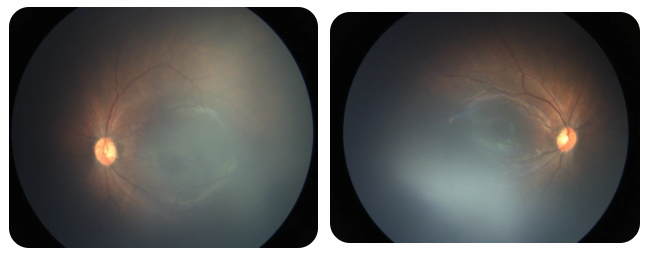

廈門眼科中心黎曉新名醫(yī)工作室曾接診一名31周出生的早產(chǎn)兒,出生體重僅1300克。由于家長缺乏篩查意識,直到孩子5個月大時眼睛仍不會追光,才前來就診。檢查發(fā)現(xiàn),患兒ROP已進展至4B期,因纖維血管增殖牽拉導致視網(wǎng)膜脫離,錯過了最佳治療窗口。盡管黎曉新教授團隊成功實施了玻璃體切割手術(shù),孩子的視力仍存在不可逆損傷。此后,孩子開啟了長期隨診復查、治療的“護眼征程”,目前其右眼矯正視力為0.6,左眼為0.8。

近期術(shù)前檢查:

早產(chǎn)兒視網(wǎng)膜病變

術(shù)后復查: